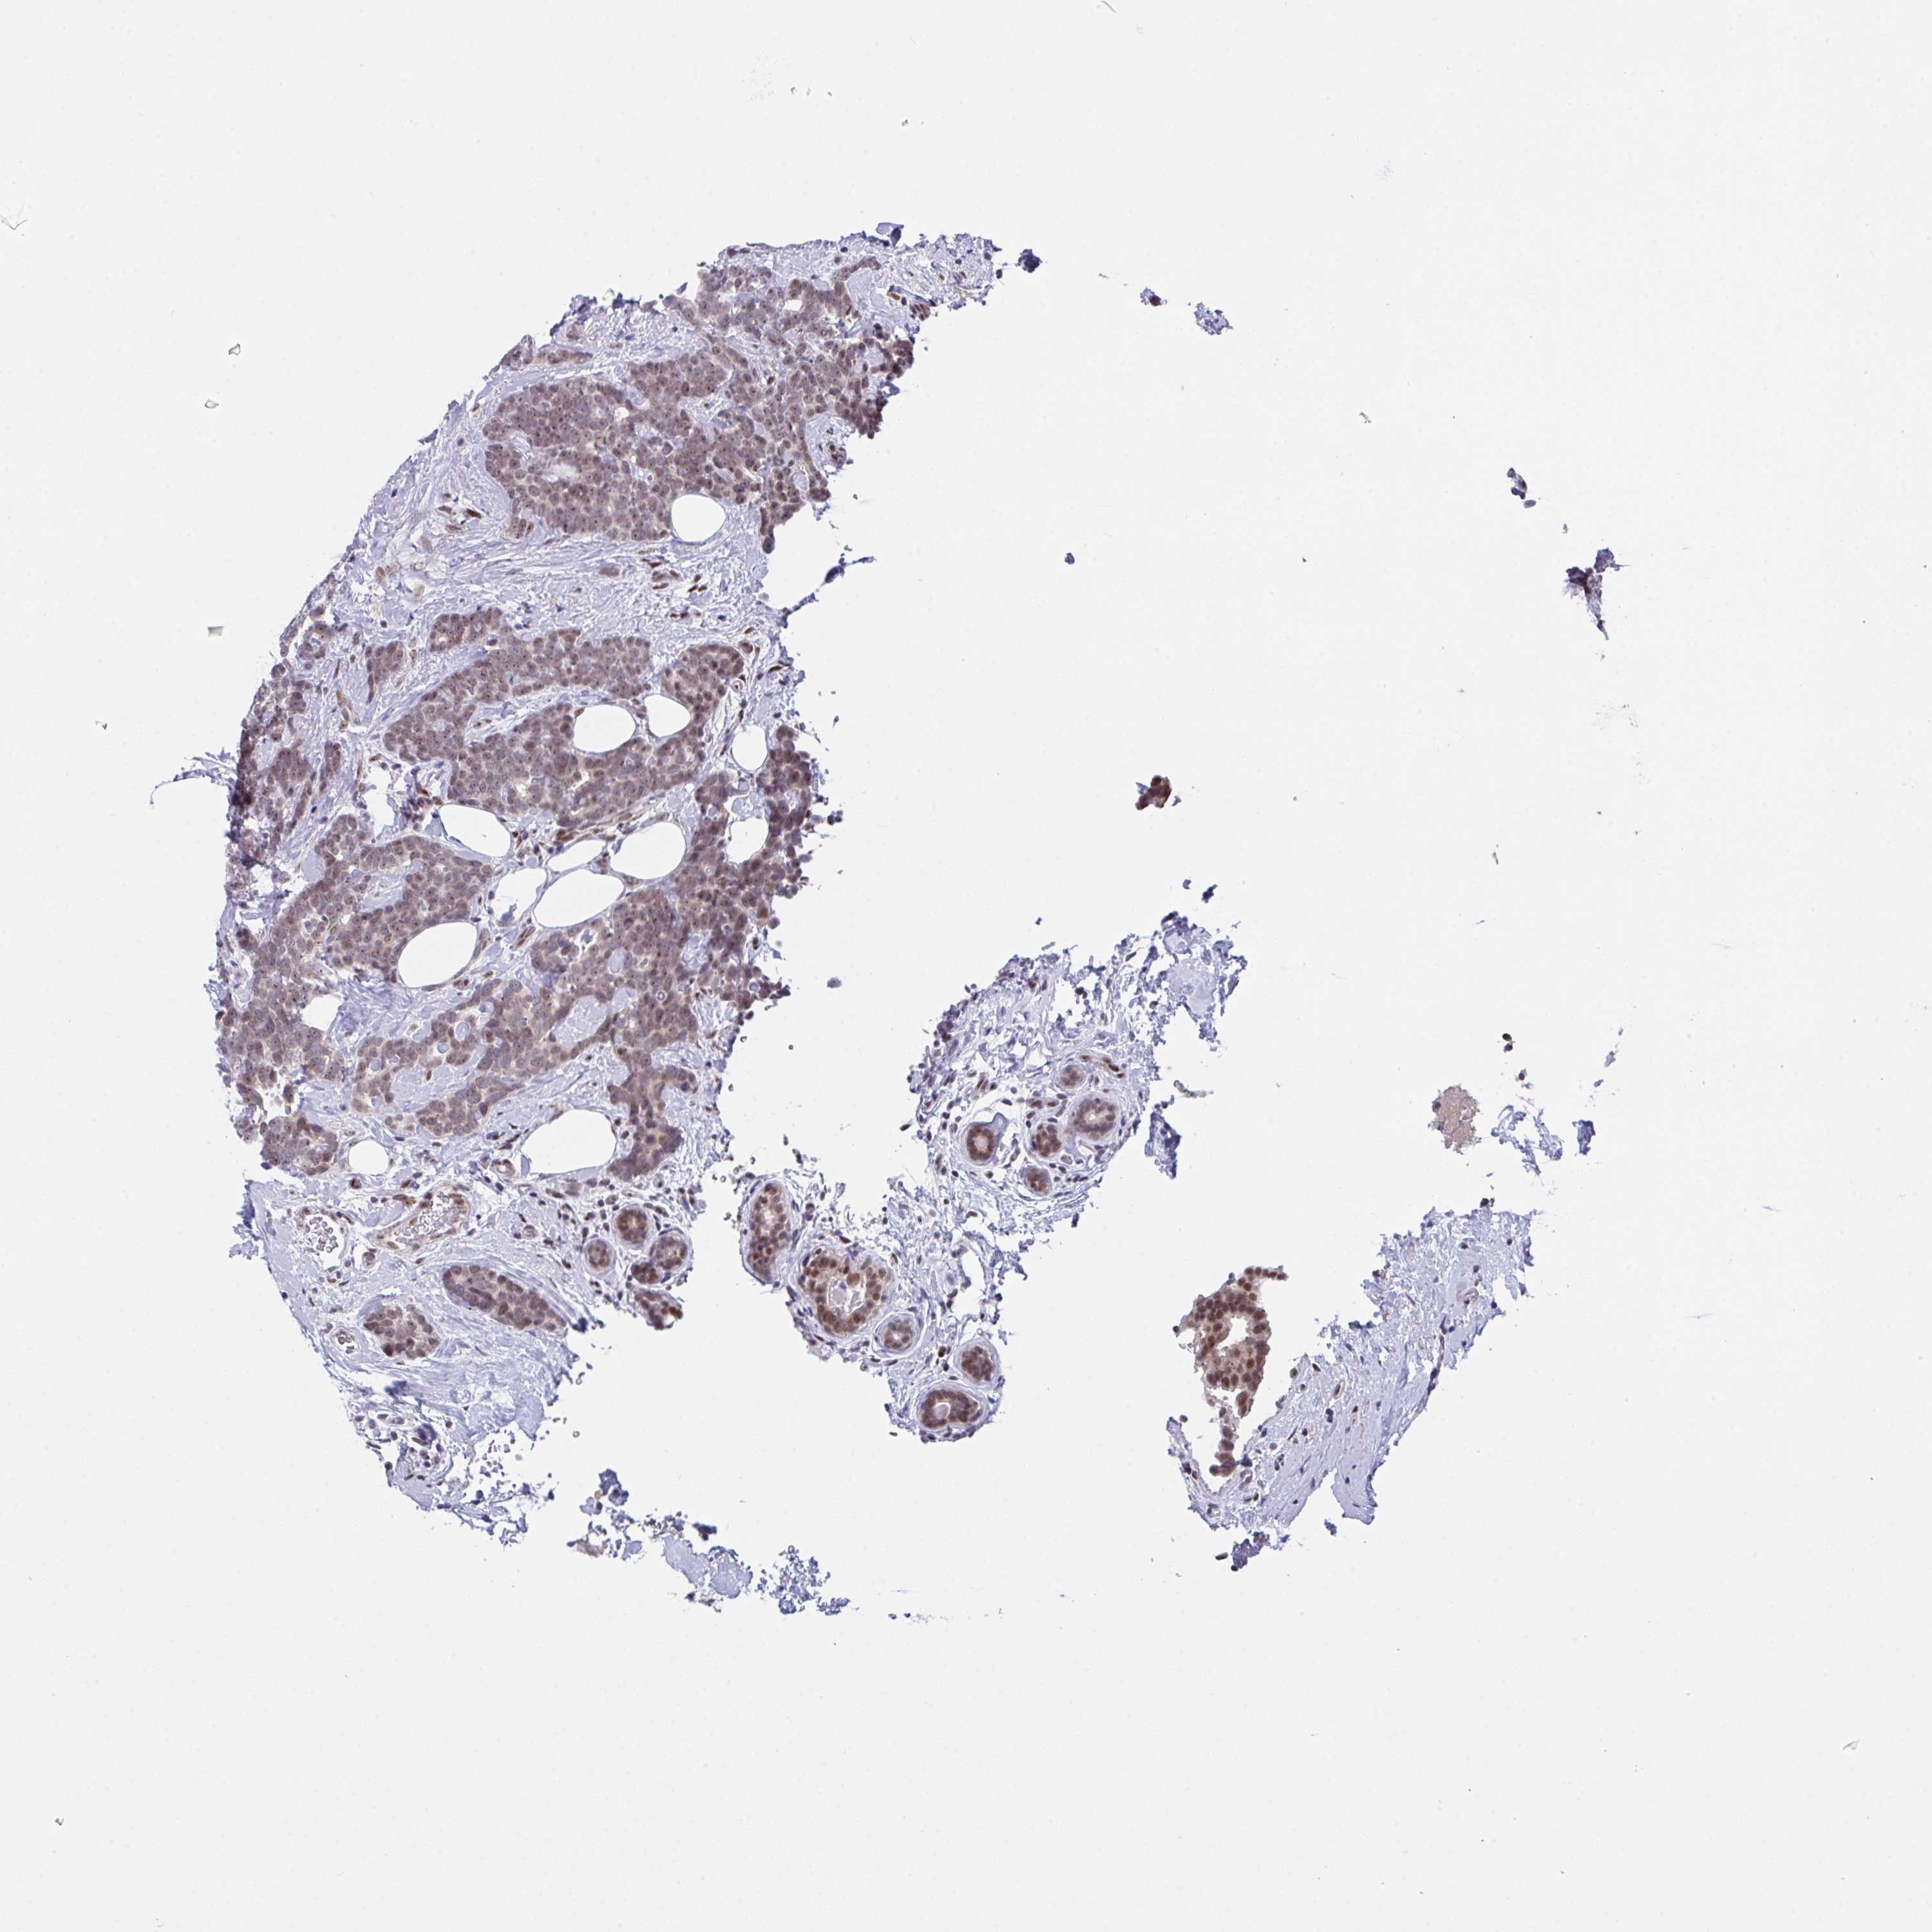

CANCER BREAST CANCER Show tissue menu

BRCA TCGA BRCA VALIDATION PROTEIN EXPRESSION

Breast cancer

Human cancer

Breast invasive carcinoma